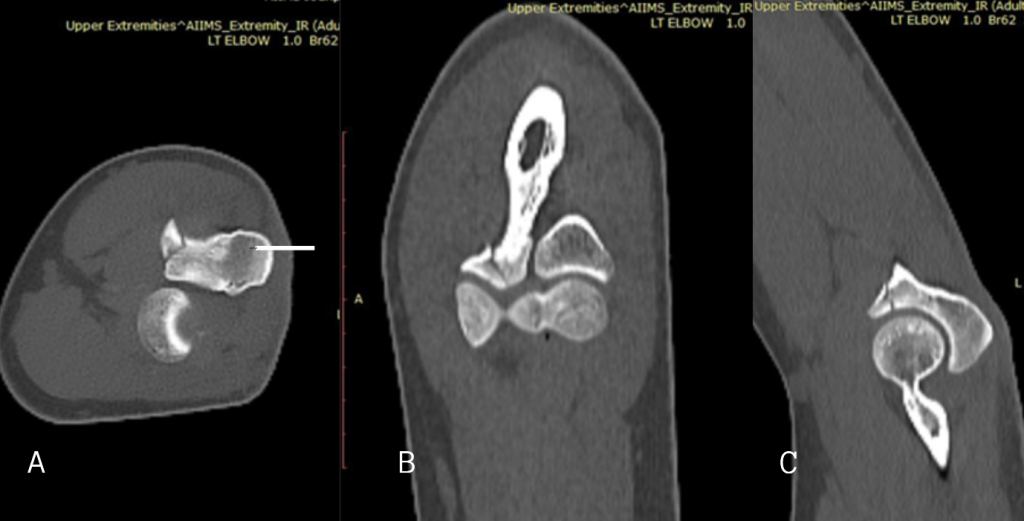

He was planned for and underwent closed reduction and internal fixation with one headless compression (Herbert) screw (Titanium, 2.7 mm) for left scaphoid fracture and closed reduction and internal fixation with one Herbert screw (Titanium, 3.5 mm) for right scaphoid fracture (Fig. 4). A volar approach was used bilaterally. Under fluoroscopic guidance, Herbert screws (2.7 mm on the left and 3.5 mm on the right) were inserted following pre-drilling and countersinking. Screw trajectory was central, ensuring optimal compression across the fracture plane. Screw positioning was confirmed intraoperatively. Bone quality was good, and there was no need for bone grafting. No intraoperative complications occurred. The bilateral nature of the scaphoid fractures also increased operative time and required special attention to patient positioning, draping, and access, as both upper limbs were involved. In addition, significant soft-tissue edema from the high-energy trauma made dissection and exposure more difficult and increased the risk of soft-tissue complications.

Figure 4: Post-operative X-rays of bilateral wrist with bilateral scaphoid fixation with Herbert screw. Anteroposterior (a) and lateral (b) view of left wrist and anteroposterior (c) and lateral (d) view of right wrist.